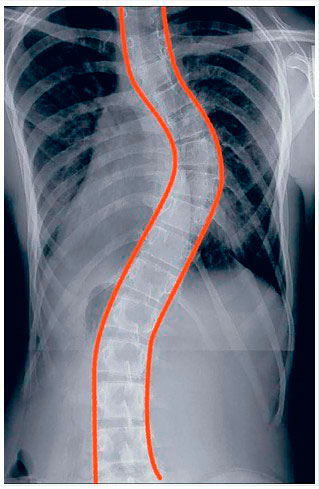

La columna vertebral vista de frente o de espalda debe estar recta. Cuando aparece una escoliosis se aprecia un desplazamiento lateral de la columna hacia la derecha o hacia la izquierda de más de 10º asociada a una rotación vertebral.

Aunque la anomalía más evidente se manifiesta en el plano frontal, la rotación vertebral hace que la escoliosis sea una deformidad tridimensional. |

¿Cómo se ve la escoliosis en la radiografía?

- La escoliosis viene definida por la región de la columna vertebral donde surge la curva (columna torácica alta, columna torácica o columna lumbar).

- La escoliosis puede localizarse en uno o más segmentos: curva simple, curvas dobles o triples.

- La dirección de la curva puede ser derecha o izquierda.